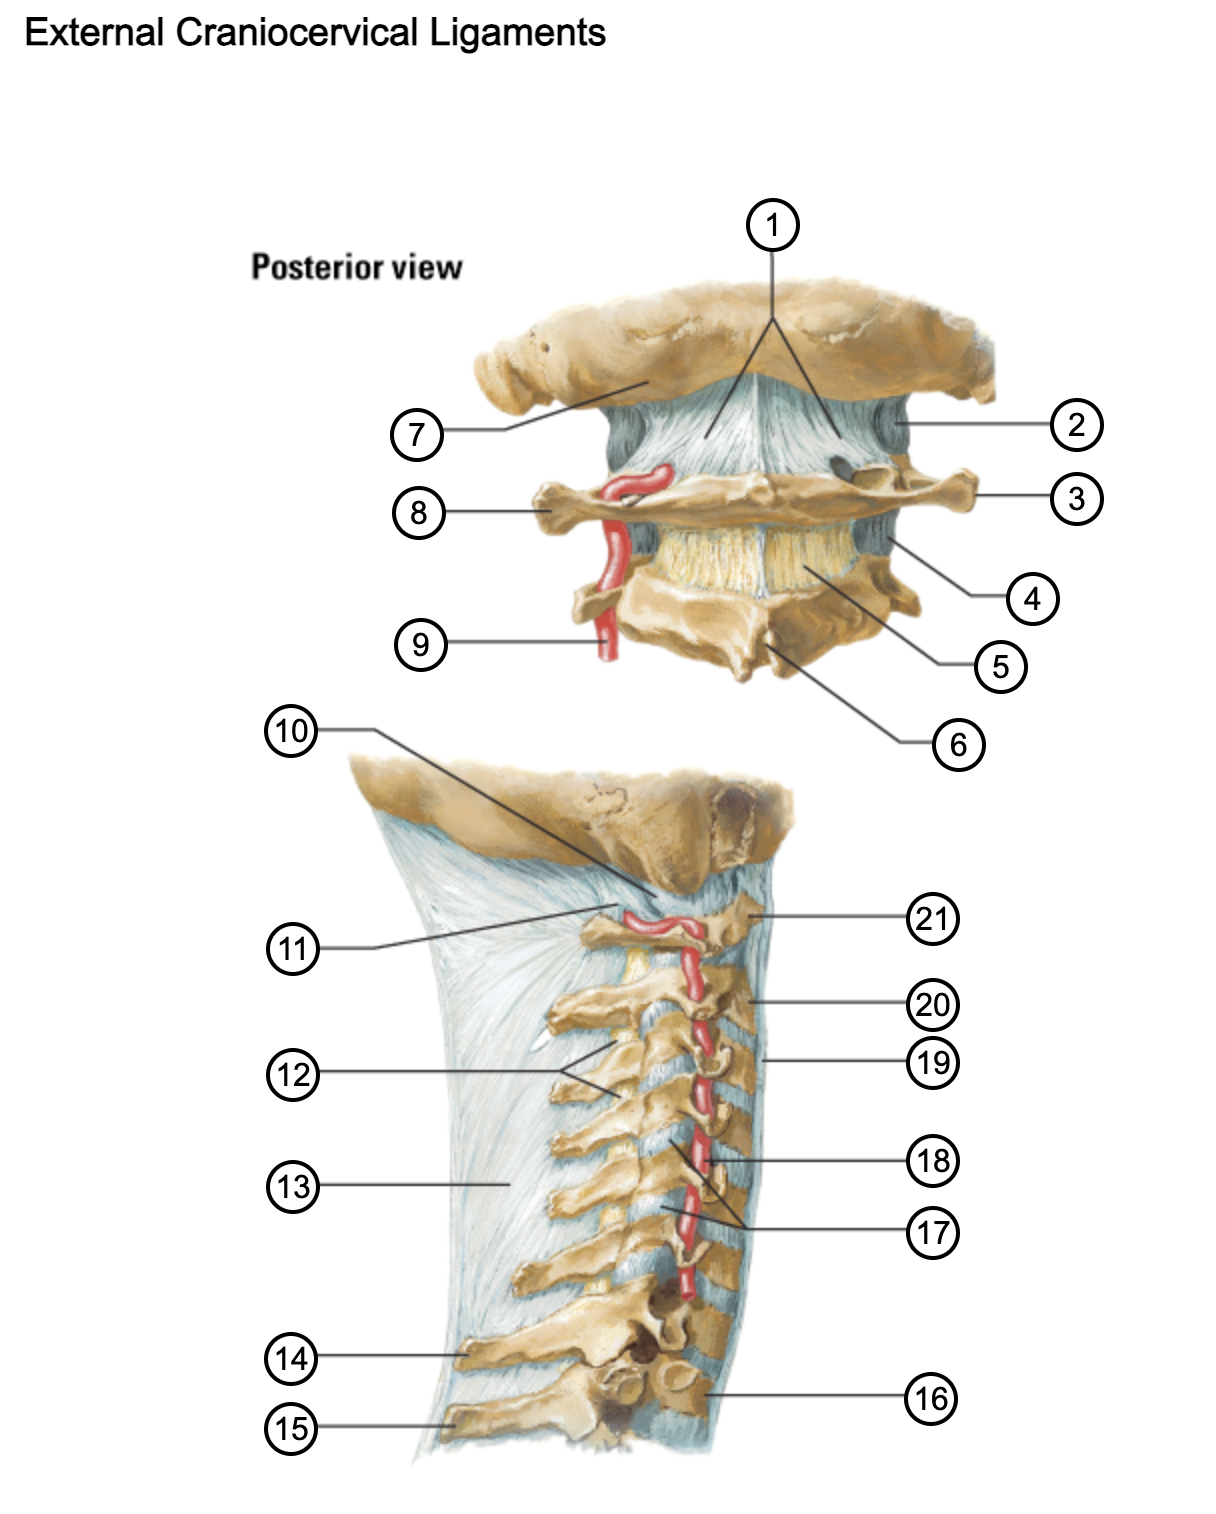

1

posterior antlantooccipital membrane

2

capsule of atlantooccipital joint

3

transverse process of atlas (C1)

4

capsule of lateral atlantoaxial joint

5

ligamenta flava

6

spinous process

7

occipital bone

8

transverse process of atlas (C1)

9

vertebral artery

10

capsule of atlantooccipital membrane

11

posterior atlantooccipital membrane

12

ligamenta flava

13

nuchal ligament

14

spinous process of C7 vertebra

15

spinous process of T1 vertebra

16

T1 vertebra

17

zygapophysical joints (C4-5 and C5-6)

18

vertebral artery

19

anterior longitudinal ligament

20

body of axis

21

Atlas (C1)